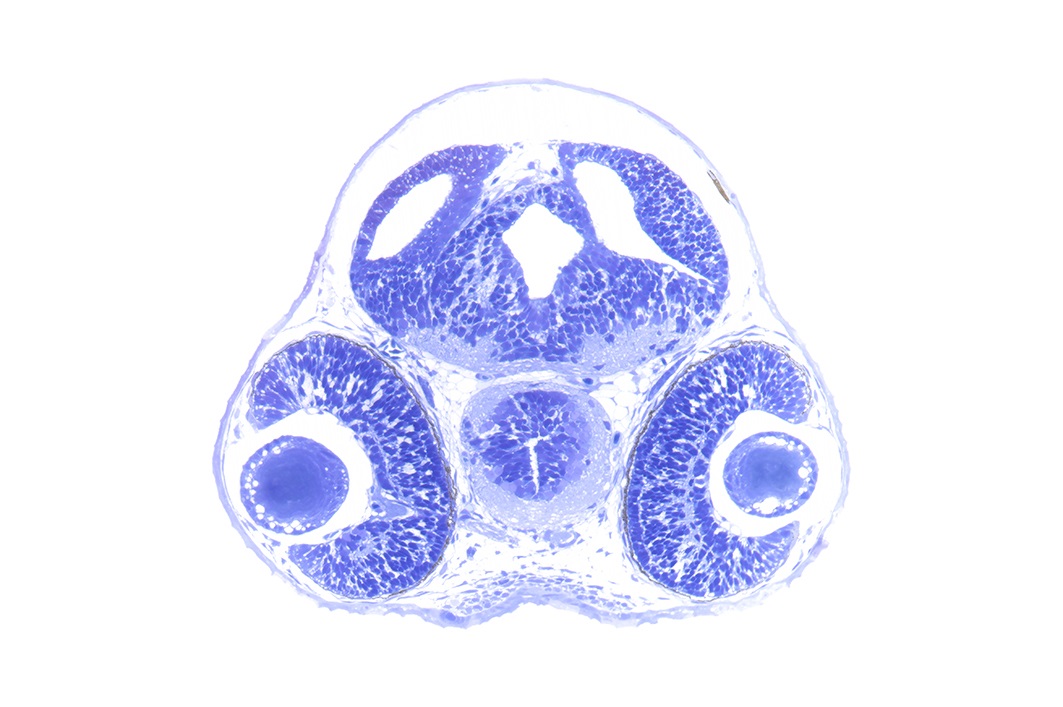

Hard Tissue Histology and Medical Device Studies

The histological analysis of hard tissues, such as bones and mineralised tissues, and of structures containing medical devices, stents or implants can be challenging. LAMP can assist researchers in developing a workflow for the processing and examination of such material, including the provision of contacts to specialised laboratories.

Bächinger D, Peyton B, Neubauer J, Dharmarajan A, Zhu M, O'Malley JT, Kallupurackal V, Senese S, Brown A, Wunderlin S, Kreutzer S, Weiss NM, Richter H, Dalbert A, Röösli C, Kipar A, Varga Z, von Rechenberg B, Amr SS, Eckhard AH, 2026. Integrated histology and molecular profiling of postmortem human auditory and vestibular organs via a poly (methyl methacrylate)-based workflow. J Assoc Res Otolaryngol. 2026 Feb 23. doi:10.1007/s10162-026-01032-4

from: Bächinger et al., 2026. doi: 10.1007/s10162-026-01032-4